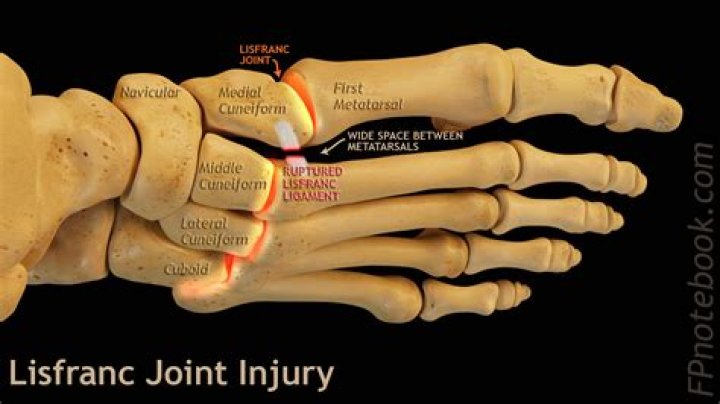

What does Lisfranc mean?

The Lisfranc joint is the point at which the metatarsal bones (long bones that lead up to the toes) and the tarsal bones (bones in the arch) connect. The Lisfranc ligament is a tough band of tissue that joins two of these bones. This is important for maintaining proper alignment and strength of the joint.

Where is the Lisfranc ligament?

The Lisfranc ligament is a large band of plantar collagenous tissue that spans the articulation of the medial cuneiform and the second metatarsal base.